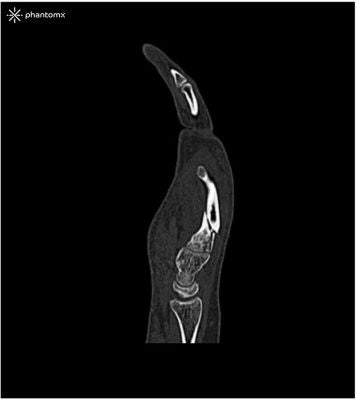

This phantom is created from real patient data and is manufactured using the latest technology. Bones, vessels and soft tissue are displayed authentically with realistic CT values for all tissues at 120 kVp tube voltage in the CT. If the phantom is to be used primarily with other tube voltages (e.g. 100 kVp), the calibration of the CT values can be adjusted accordingly if required. The phantom provides realistic tissue contrasts in X-ray imaging. Air spaces are filled by a material with about -80 Hounsfield units.

The hand phantom provides an extremely realistic simulation of a hand. Pathologies (e.g. fractures, calcifications, bones and soft tissue tumors) can be integrated on request.